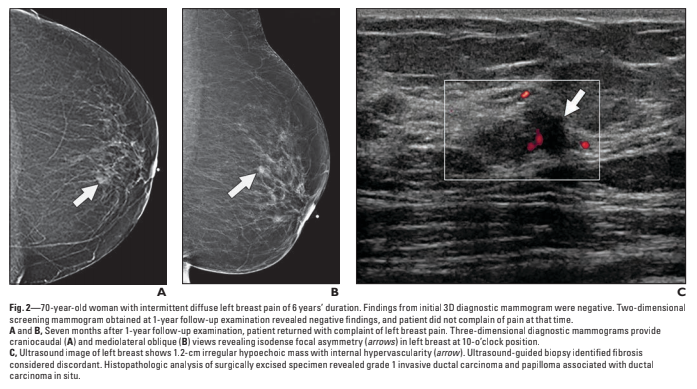

4 patients were described with breast cancer.

What did they find, and was it associated with breast pain?